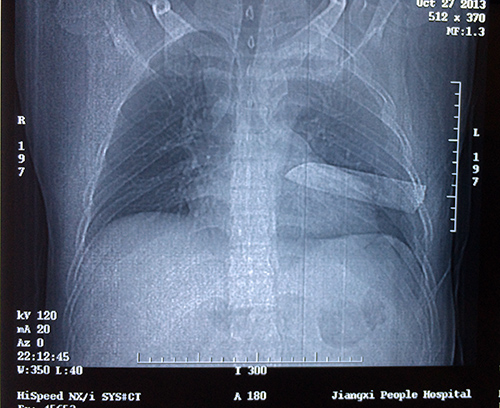

10月27日晚上9时许,省人民医院急诊科的电话突然响起,120紧急转入一名年轻病人,病人由朋友陪护到医院,鲜血染湿了他的上衣。只见他的左胸还在不断渗血,摄片显示惊人的一幕:一柄狭长的刀刃刺入了他的胸腔,10—12cm刀刃完全留置在左侧胸腔,刀柄已经断裂。

接到这名危急病人,我院打开急诊绿色通道,入院后立刻转至手术室,5分钟后心胸外科专家紧急会诊,决定马上进行手术,取出胸腔刀具,抢救病人生命。此时病人胸腔几乎都是积血,呼吸衰弱,血压下降。麻醉师周涛迅速为病人麻醉气管插管,主刀医师、心胸外科主任医师柳阳春果敢的带领主治医师林庆果敢、快速的开胸,只见刀刃贯穿左上肺、左下肺,刺破肺血管,割断背段支气管。柳阳春介绍,刀刃卡在两根肋骨之间,深深的切进肋骨中才没有进一步刺入,“如果再进一点,伤及胸主动脉,病人必定当场死亡。”

手术中进行了左侧血气胸清除、肋间血管缝扎、上下肺叶部分切除、肺血管缝扎、刀具取出、左下肺支气管缝扎,直至凌晨3点半才结束,成功取出刀具。